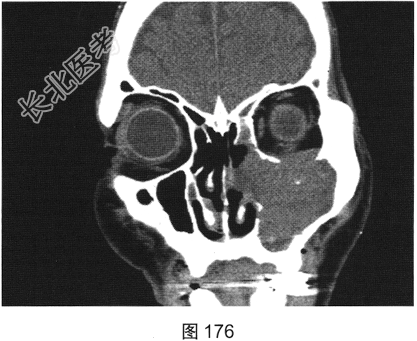

- [材料题] 患者男性,75岁。左侧颌面部肿胀6个月,局部压痛,伴有左侧鼻塞、流涕。CT检查结果如图173~图176所示。

- 简答题1、请问该患者CT表现是什么?

- 简答题2、请问最符合该患者的初步诊断是什么?